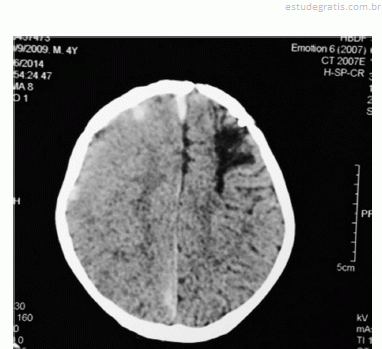

Observe a figura a seguir.

Paciente com quatro anos de idade, portador de hemofilia A, com inibidor de alta resposta em alto título (60 unidades Bethesda), apresenta, há 15 dias, queda da própria altura, quadro de náusea, cefaleia e crise convulsiva. A imagem da tomografia de crânio sem contraste mostra-se com o aspecto apresentado na figura. Nessa situação hipotética, o tipo de terapia indicado para o tratamento de urgência do paciente é a reposição de